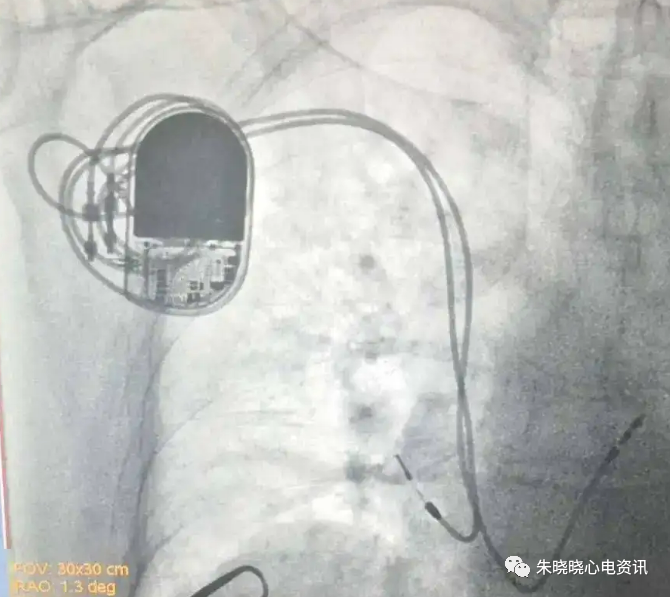

百多力起搏器接线部分和餐桌上的碗筷组合相似(图11)

图11 百多力起搏器

百多力起搏器怎么样“贴心”的通过胸片识别起搏器方法,让你秒懂_https://www.jmylbn.com_新闻资讯_第13张